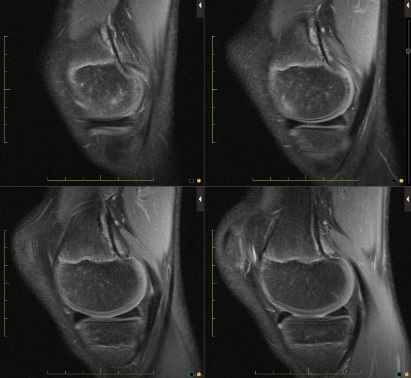

Figure 1 for case Cortical desmoid

Figure 1